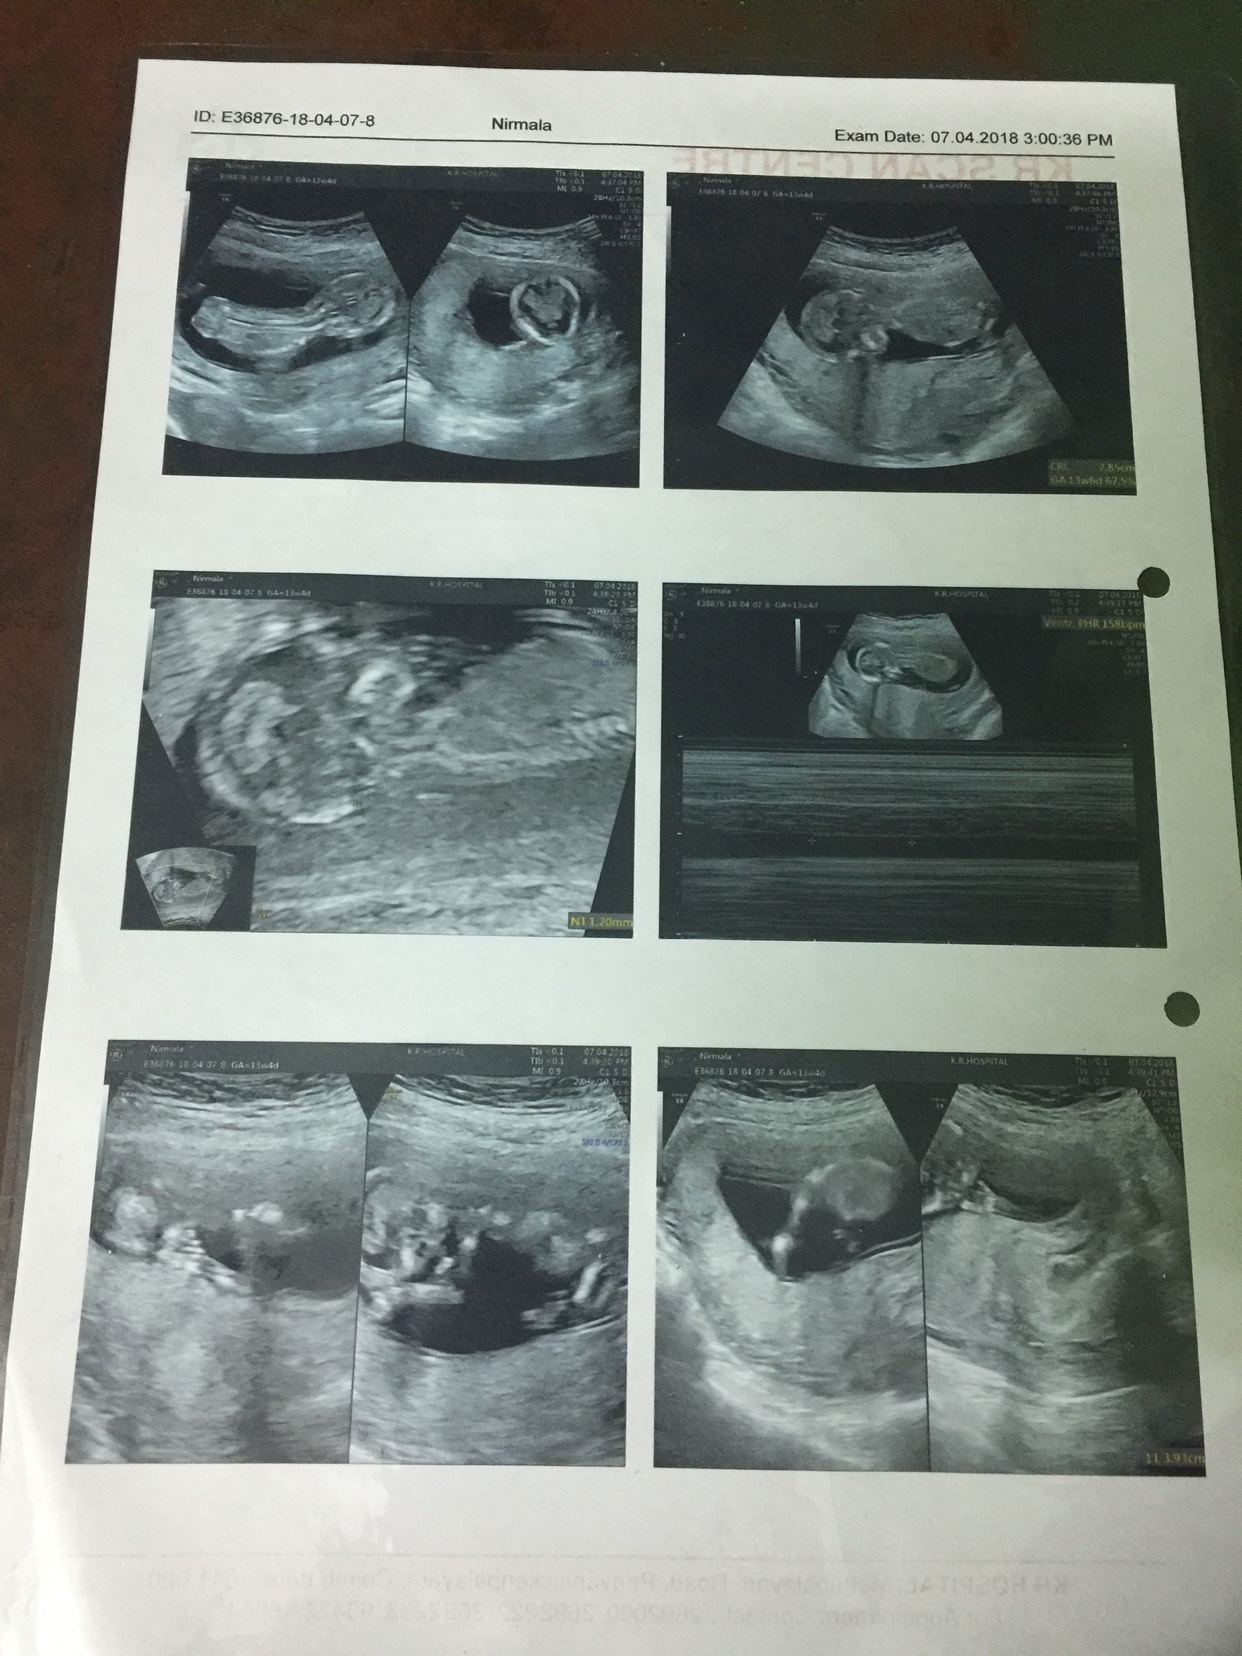

Opinions please boy or girl ?

Attachment 39228

Awaiting for all your responses